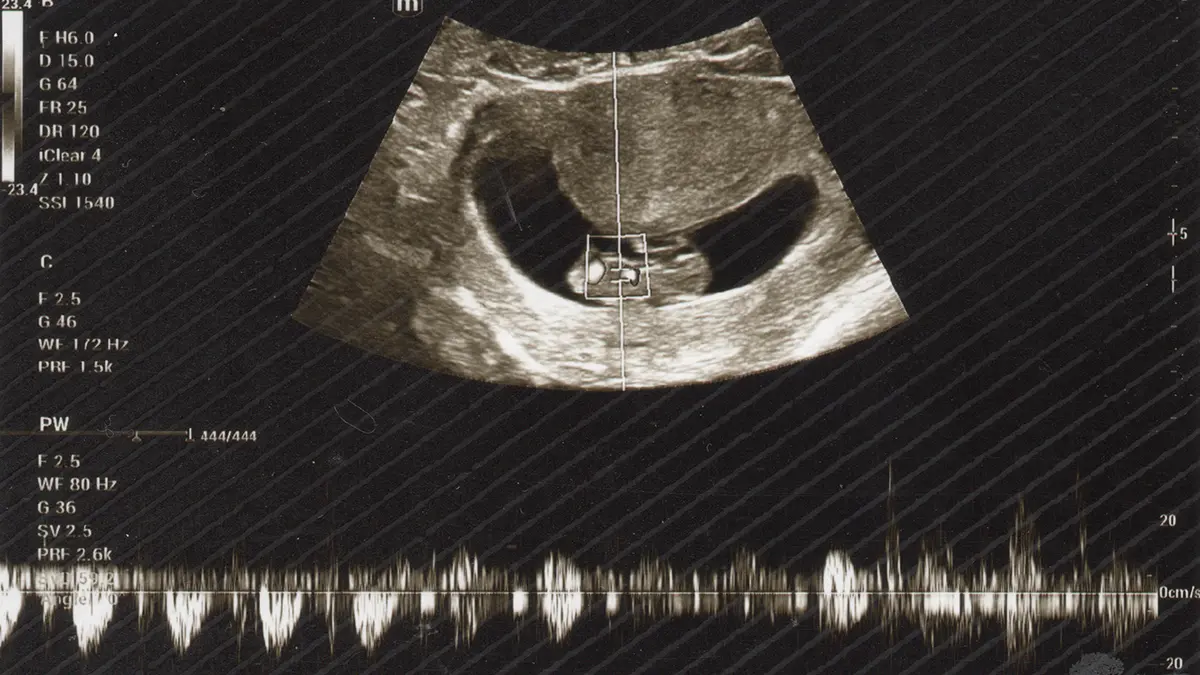

Kemarin malam itu, dokter itu bertanya, apakah ingin mendengar suara detak jantungmu. Tentu saja kami ingin mendengarkannya. Dokter kemudian menggunakan perangkat ultrasonografi miliknya di perut ibumu. Kemudian terdengarlah. suara degup yang ritmis. Monitor menunjukkan sebuah grafik.

Sulit rasanya menggambarkan suara itu melalui kata-kata. Apalagi menggambarkan perasaan. Bahagia dan haru jelas bercampur saat mendengar suara degup ketika jantungmu berdetak. Itulah saat pertama kali kami mendengar detak jantungmu. Walau kami juga tahu, Allah belum meniupkan ruhmu.

Tidak hanya itu, dokter yang juga petembak itu memperlihatkan apa yang kelak akan menjadi tangan dan kakimu. Memang masih terlihat sangat mungil. Tapi entah kenapa sudah terbayang kelak kau akan berjalan dan berlari dengan sepasang kaki itu.

Menurut kalkulasi USG, diperkirakan usiamu kemarin malam itu adalah 9 (sembilan) pekan dan 5 (lima) hari. Kami mulai berhitung, sedikit lebih dari 7 (tujuh) bulan lagi kau akan hadir. Semoga Allah SWT senantiasa memberikan perlindungan dan kesehatan, untukmu dan ibumu.